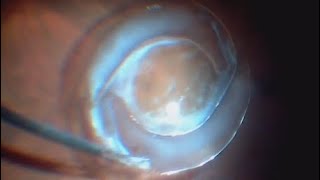

🏆Top of the line ophthalmology clinic treating all eye diseases with innovative treatment and state of the art technology